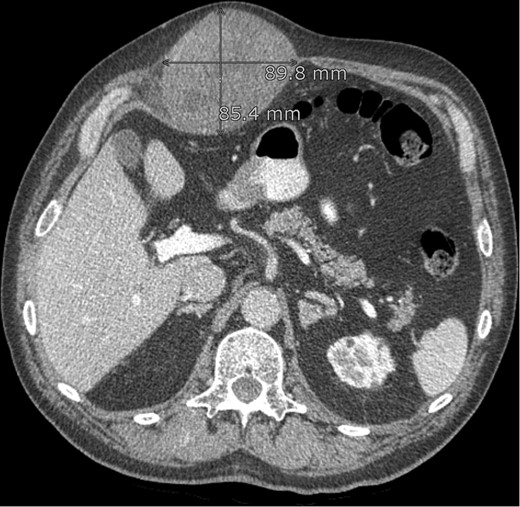

On palpation the lesion is solid elastic to the touch. An ultrasound investigation with histological biopsy was made. Histological examination showed fibroma myxoid tissue with the suspicion on nodular fasciitis. Additional CAT-scan images (Fig. 1) revealed a smooth, oval and the peritoneum-bordered tumour located medially and spreading into the rectus abdominis muscle.

CT abdomen: lesion in the abdominal wall, possibly originating from the rectus abdominis muscle.